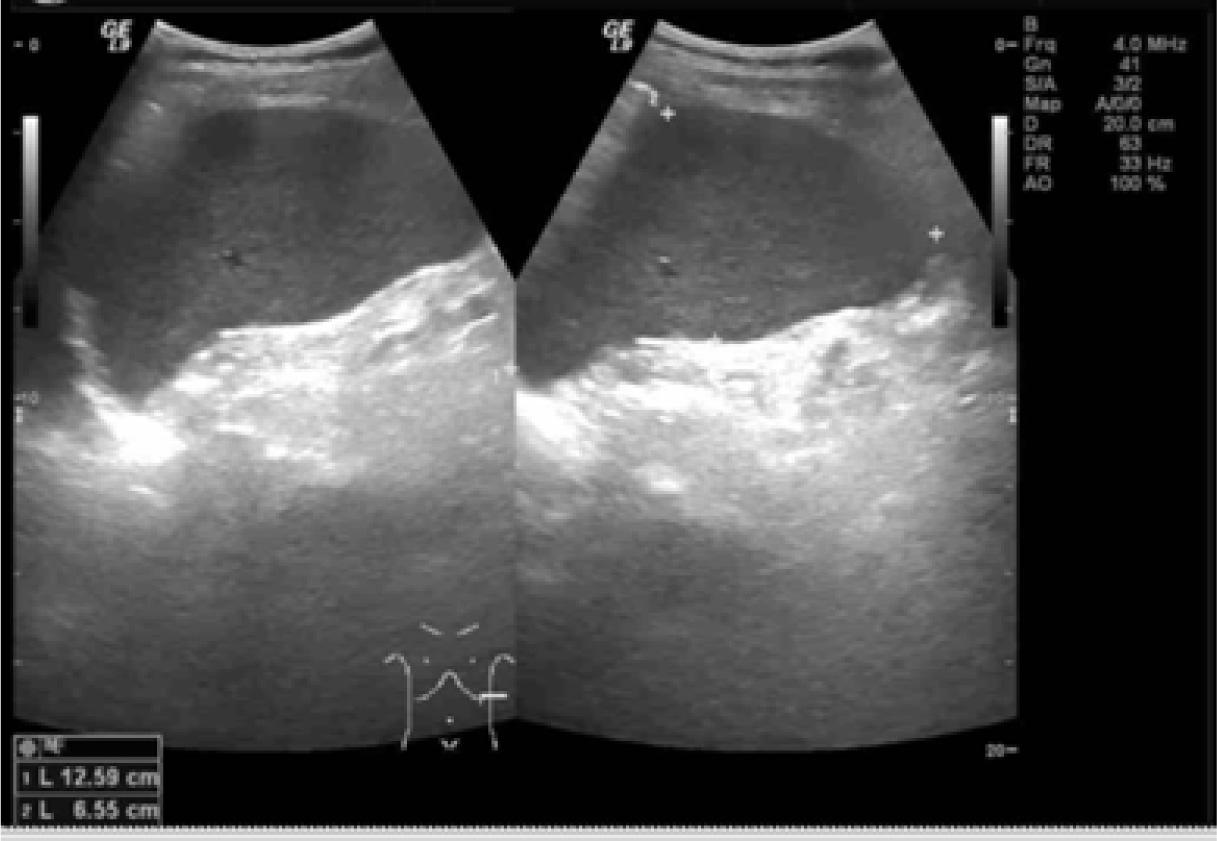

A 53 year-old Thai man presented to our emergency department with left hemiparesis and slurred speech. He had a history of hypertension, smoking, and alcohol intake. On physical examination, his respiratory and cardiovascular systems were normal. The patient had splenomegaly by palpation and confirmed by ultrasonography (Figure 1).

Ultrasound images show splenomegaly (size 6.6 cm × 12.6 cm) without a focal mass. No ascites or lymphadenopathies were noted.